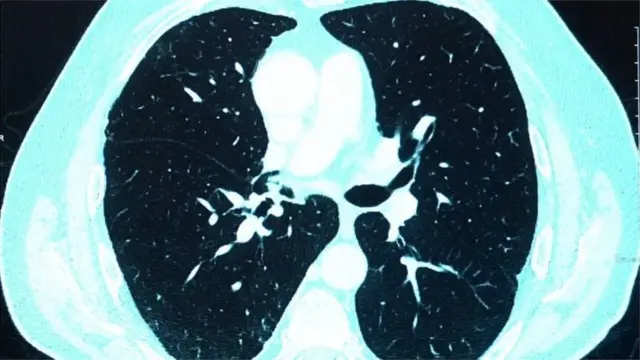

কোভিড-১৯ নামের এই রোগে প্রধানত ফুসফুস আক্রান্ত হয়।

বক্ষব্যাধি বিশেষজ্ঞ ডা. রওশন আরা খানম বিবিসি বাংলাকে বলছেন, ''করোনাভাইরাসে আক্রান্ত হওয়ার পর যাদের হাসপাতালে ভর্তি হতে হয় বা আইসিইউতে যেতে হয়, তাদের ফুসফুসের ক্ষতিটা বেশি হয়। তাদের সেই ক্ষতি কাটিয়ে উঠতে, স্বাভাবিক জীবনযাপনে যেতে অনেক সময় লেগে যায় বলে আমরা দেখেছি। তাদের জন্য পরবর্তীতে 'ফুসফুসের পুনর্বাসন প্রোগ্রাম' দরকার হয়ে পড়ে।''